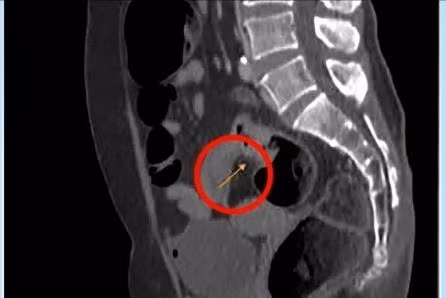

Tại bệnh viện, kết quả nội soi trực tràng của bệnh nhân cho thấy u ở lòng trực tràng phát triển gây bán tắc, dạng vòng nhẫn, thâm nhiễm cứng. Kết quả MRI 3 tesla ghi nhận thành ruột dày không đều tại chỗ nối trực tràng với đại tràng sigma (12 mm), trên 30 mm không rõ cấu trúc, tổn thương dạng không nhầy chiếm hết chu vi, gây hẹp lòng đại tràng tại vị trí này.

Chụp MRI cho thấy khối u ở trực tràng (mũi tên vàng) của bệnh nhân. Ảnh BVCC

Trong quá trình phẫu thuật, bác sĩ quan sát chưa thấy nốt di căn, u trực tràng cao co kéo thanh mạc, u to khoảng 5 cm. Bác sĩ cắt ngang trực tràng dưới khối u 4 cm, tiếp đó đưa phần trên đại tràng cùng khối u ra ngoài qua đường mổ nhỏ dưới rốn, cắt ngang đại tràng cách bờ trên khối u 15 cm. Đoạn trực tràng lấy ra dài 25 cm. Sau khi kiểm tra với thuốc nhuộm huỳnh quang ICG cho thấy máu nuôi tốt, bác sĩ tiến hành nối đại tràng với trực tràng bằng máy.